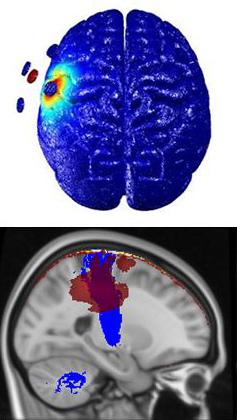

HD-tDCS 采用 4 X 1 環(huán)形電極配置,陽(yáng)極置于患側(cè)半球C3或C4,周圍四個(gè)陰極,以聚焦電流于手部運(yùn)動(dòng)皮層區(qū)域。這種配置能更精確地調(diào)節(jié)目標(biāo)皮層的興奮性,促進(jìn)神經(jīng)可塑性(圖1)。

圖1 HD-tDCS改善中風(fēng)患者運(yùn)動(dòng)通路功能和上肢恢復(fù)示意圖